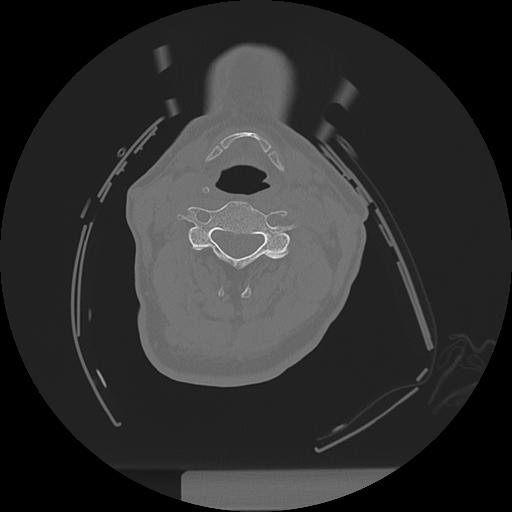

11 HUESO,,Axial,2.0,HUESO,,